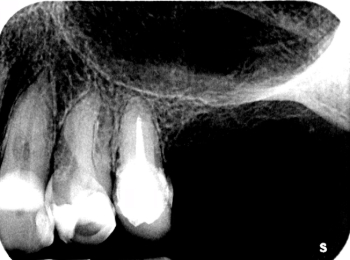

Röntgen Krone insuffizient

15: Krone insuffizient, apikale Aufhellung.

Röntgen Wuzelkanal

15: Zustand nach Revision und Behandlung des zweiten Wurzelkanals.